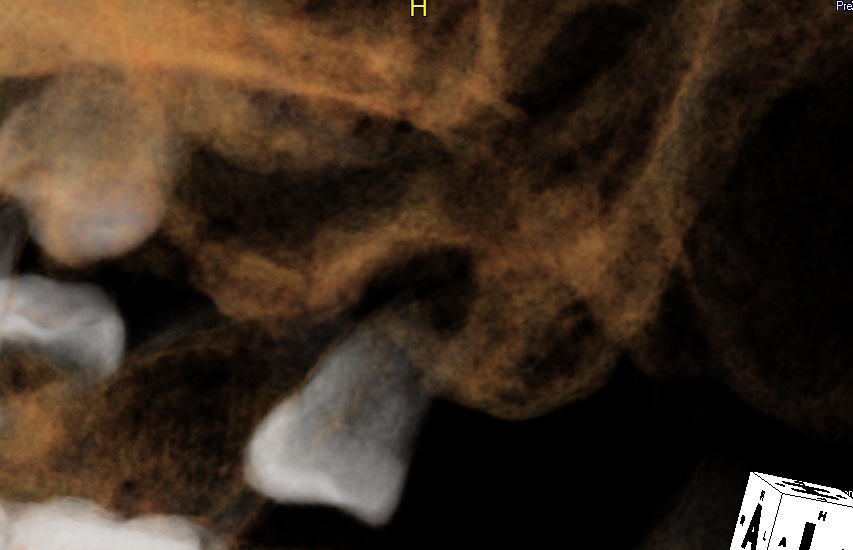

Figure on the left is a 3-D image showing that the socket of the second molar is tapered. Figure on the right is a sagittal section through the msiodistal aspect of the tooth #15. The apical dimension is less than 5 mm, smaller than the apical diameter of 8x11 mm tapered implant (5.5 mm). Furthermore, can we lift the sinus floor to gain apical friction and use 8x14 mm tapered implant? Return to main article